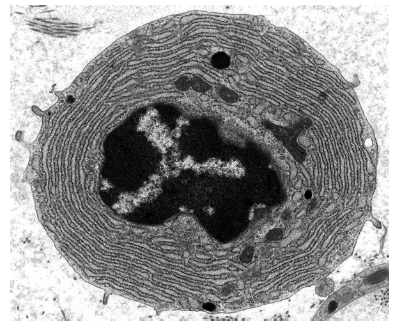

The electron micrograph shows a type of blood cell.

What can be concluded from the electron micrograph?

The cell secretes products that are toxic to pathogens.

The cell synthesises a large quantity of proteins.

The cell synthesises large quantities of antigens.

The cell digests pathogenic bacteria.